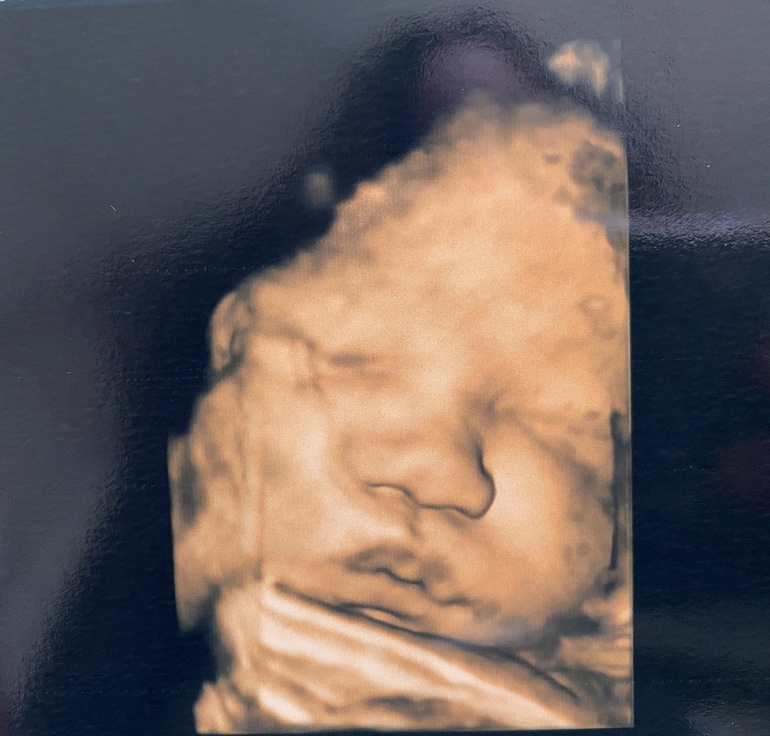

УЗИ, КТГ, доплерБыла сегодня на узи . Срок 38.3 и по месячным и по узи . Шейка 32 мм, зев сомкнут )степень зрелости Плаценты 2-3 ст . доча 3300 и 50 см . После узи пошла на осмотр к врачу . Шейка длинная , пропускает палец ) как долго я ещё буду хоть и есть ли шанс родить в пдр ?😄я уже отчаялась . Доче там видимо и так неплохо ) но ходить до 42 недель вообще нет никаких сил 😩

Милашка , блин , у нас нет такого УЗИ ,чтоб так четко ... Хотя осталось то не так много ,можно потерпеть.